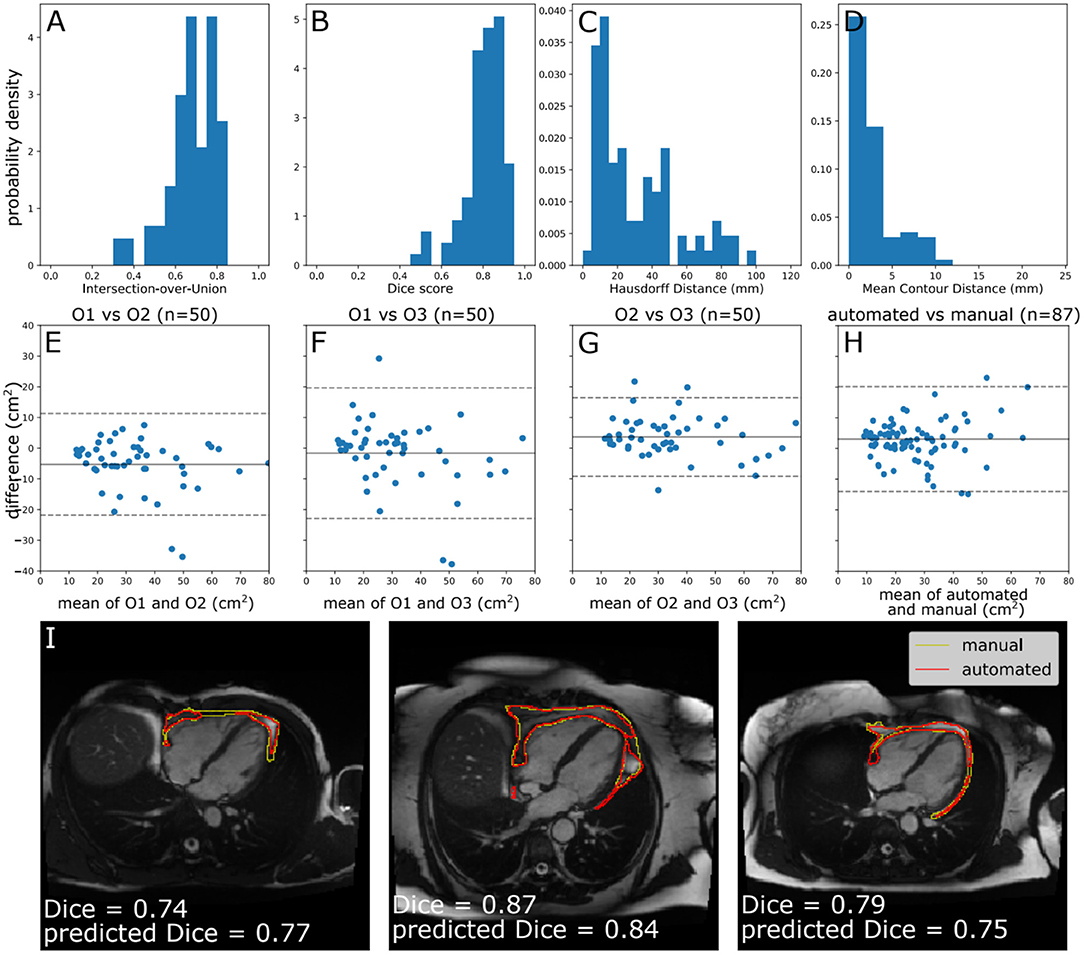

Metrics for Assessment of Segmentation Agreement, Inter-observer Variability, and Model Performance

We evaluated agreement between manual segmentations of different expert observers (AB, ZRE, and SEP) and between manual and automated segmentation. When multiple MC samples are drawn from the stochastic neural network, their level of agreement is correlated with the quality of the consensus segmentation (24). We expressed level of segmentation agreement using metrics based on the well-known intersection-over-union (or Jacard Index) and the Dice score. Thus, we used four metrics for agreement between segmentations: the Dice score, Intersection-over-Union (IoU) metrics for overlap, the mean contour distance, and the symmetric Hausdorff distance (compares the closeness of foreground voxels borders). Both of the overlap metrics are bounded between 0 and 1, with 0 representing no overlap and 1 representing perfect overlap. For both of the distance metrics, lower distances represent closer agreement between segmentation results. In line with previous literature pertaining to QC (24, 28), we classified segmentation accuracy as poor, medium, or good based on Dice scores of <0.6, 0.6–0.8, and ≥0.8 respectively.

Evaluation of Automated CMR PAT Segmentation Model Performance

The performance of the automated segmentation within the test set relative to manual segmentations was good and very similar to the agreement between human observers (mean Dice score = 0.8). This was the case both for raw segmentation metrics (Table 1) and under Bland–Altman analysis (Figures 3E–H). Arguably, this is the best performance that may be achieved by an automated segmentation algorithm and reflects the inherently challenging nature of the PAT segmentation task. A few cases (n = 4, 4.5%) had poor segmentation quality (Dice score <0.6) (Figures 3A–D) and very large Hausdorff distances. This underlines the importance of the in-built QC feature, which would flag such cases. We also successfully applied the automated segmentation to the whole UKB imaging cohort (n = 45,519); 94.3% of cases (n = 42,928) had predicted Dice score of medium or good quality (mean predicted Dice score = 0.77). Example segmentation results from the UKB test dataset can be seen in Figure 3I. The automated segmentation also performed well in the external EVINCII dataset, with the majority of studies having medium/good segmentation quality (n = 103, 94.4%), with an overall mean predicted Dice score of 0.78 (Figure 4A). Running on a laptop PC with an Intel® Core™ i7-1165G7 processor, using a MC sample size (N) of 15, the model and QC step took 2.1 s, including image pre-processing and final estimation of Dice score.

Figure 3. Model performance. (A–D) Histograms of standard segmentation performance metrics on the test set (n = 87). (E–H) Bland–Altman plots of PAT area between manual measurement between measurements by different human observers, and a human observer (O1) and automated measurement. The x-axis denotes the average of two measurements and the y-axis denotes the difference between them. The dark line is the mean difference, and the dashed lines show ±1.96 standard deviations from the mean. (E–G) show the inter-observer variability evaluated by three observers (O1–O3) on a randomly selected subset of the manually contoured training set (n = 50 subjects). (H) shows the agreement between automated and manual measurements in the manually contoured test set (n = 87 subjects). (I) Example segmentations from the test set, with annotations showing Dice score and the predicted Dice score. Images reproduced with permission of UK Biobank.